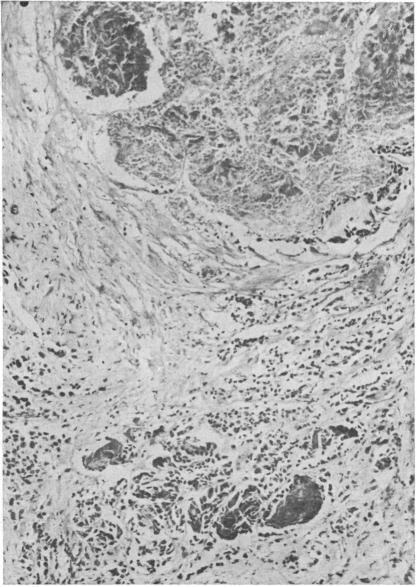

During the past six years 40 patients have been treated with fast neutrons for inoperable adenocarcinoma of the stomach. A number of these patients have been studied in detail both radiologically and pathologically with regard to the effects of fast neutrons on both the tumour and normal stomach. After treatment there was a constant reduction in size of the stomach capacity when compared with a control group and the motility of the stomach was lost. Mucosal changes, which were noted radiologically, appeared to be dose related. Histologically most of the tumour was destroyed. Small clumps of cells were, however, found in all except one of the patients but only in areas of the stomach which had not received the standard dose. Marked fibrosis occurred and it is our impression that the amount of fibrosis is in excess of that seen with other forms of radiotherapy.

在过去六年中,40例无法手术的胃腺癌患者接受了快中子治疗。其中一些患者就快中子对肿瘤和正常胃部的影响进行了详细的放射学和病理学研究。与对照组相比,治疗后胃容量持续减小,且胃动力丧失。放射学观察到的黏膜变化似乎与剂量相关。组织学检查显示大部分肿瘤被破坏。然而,除1例患者外,所有患者均发现有小细胞团块,但仅存在于未接受标准剂量照射的胃部区域。出现了明显的纤维化,我们的印象是纤维化程度超过了其他形式放疗所见。